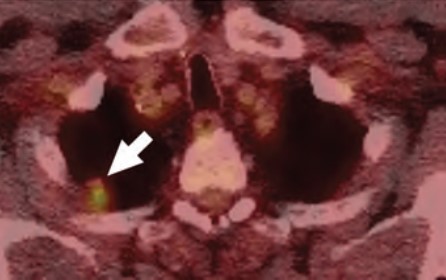

At the individual level, some of the barriers to awareness include unfamiliarity with LCS as a health preventive service tool (Fig. 2), unawareness of the new USPSTF and Centers for Medicare & Medicaid Services (CMS) recommendations for LCS, unfamiliarity with insurance coverage and costs, uncertainty about available accredited LCS programs, lack of culturally appropriate information, and lack of information at an appropriate health literacy level [8–10].